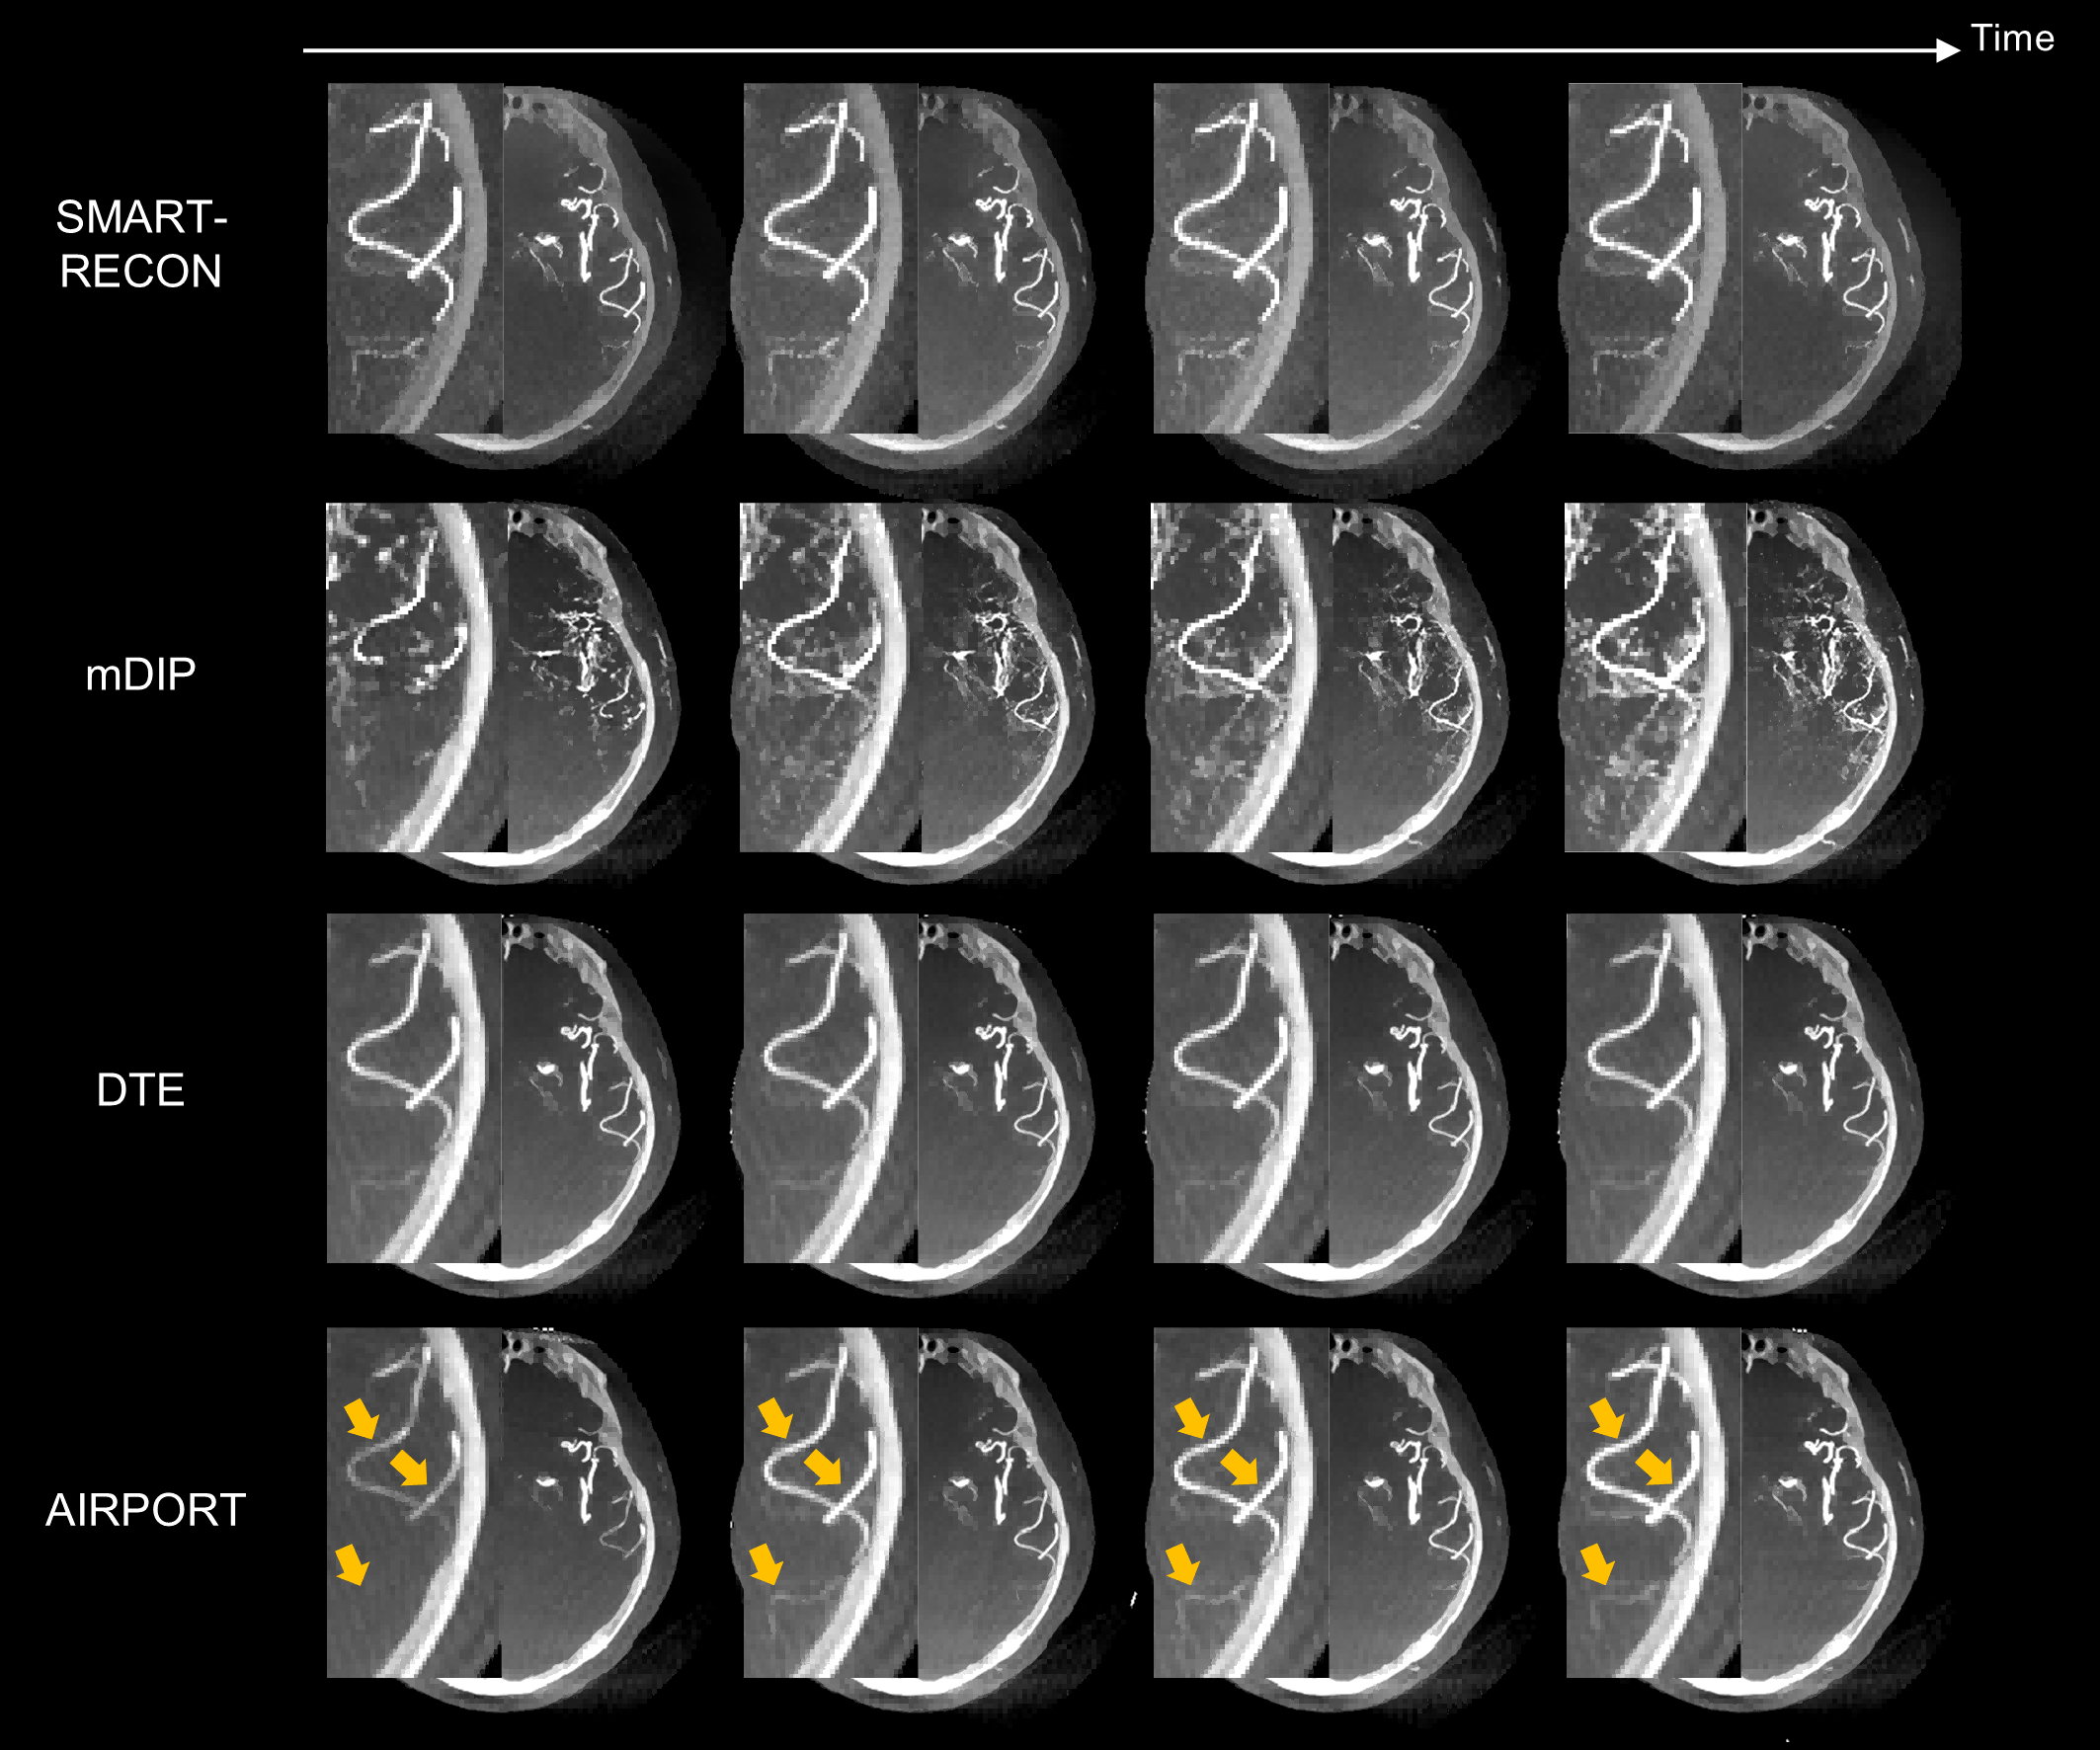

图3. 人体实验数据结果。如黄色箭头所示,提出的AIRPORT方法能够正确地重建由造影剂注射导致的动脉强度值的变化。